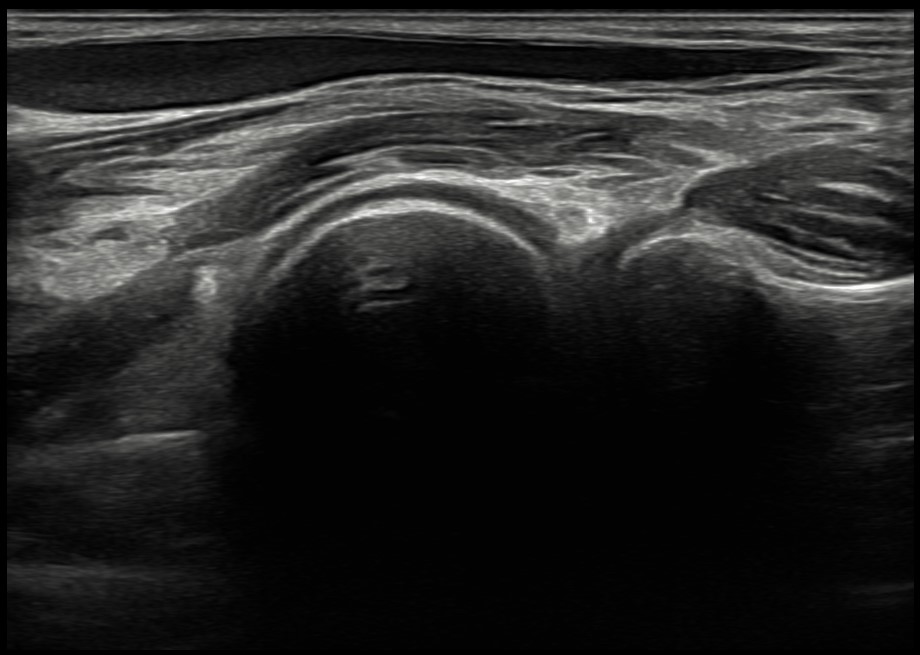

La venopunción ecoguiada se muestra como una técnica segura que ayuda a fomentar medidas de prevención cuaternaria y mejora el control emocional de los pacientes. Actualmente esta técnica se encuentra casi exclusivamente ligada a servicios como urgencias hospitalarias o UCI. Su implementación dentro de la Atención Primaria supone un proceso novedoso y destacable. Hoy en día, las enfermeras especialistas en Familiar y Comunitaria no cuentan en su periodo de residencia con una formación adecuada en esta técnica, por lo que el modelo de formación de formadores y su posterior integración en el EAP se plantea como un proceso innovador y pionero en Atención Primaria del Servicio de Salud del Principado de Asturias. Para iniciar la implementación de esta técnica, se ha realizado formación teórica y práctica conjunta entre residentes de medicina y enfermería.

La venopunción ecoguiada se muestra como una técnica asequible y útil en Atención Primaria, especialmente en casos de venopunción dificultosa.